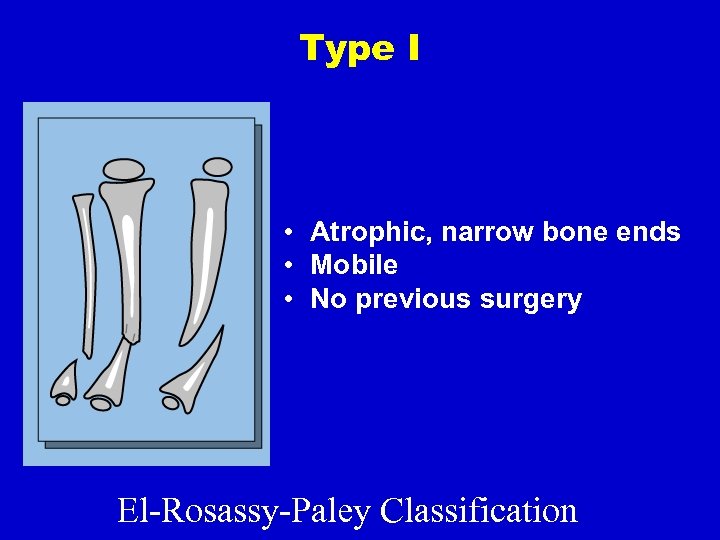

Type I • Atrophic, narrow bone ends • Mobile • No previous surgery El-Rosassy-Paley Classification